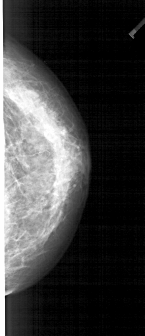

A_1938_1.LEFT_CC

LEFT_CC LINES 4651 PIXELS_PER_LINE 1951 BITS_PER_PIXEL 12 RESOLUTION 43.5 OVERLAY

FILE: A_1938_1.LEFT_CC.OVERLAY

TOTAL_ABNORMALITIES 1

ABNORMALITY 1

LESION_TYPE MASS SHAPE IRREGULAR MARGINS SPICULATED

ASSESSMENT 5

SUBTLETY 2

PATHOLOGY BENIGN

TOTAL_OUTLINES 2

BOUNDARY

CORE